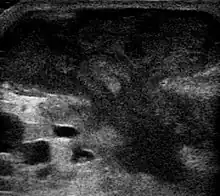

They are usually caused by a bacterial infection.[10] Often many different types of bacteria are involved in a single infection.[8] In many areas of the world, the most common bacteria present is methicillin-resistant Staphylococcus aureus.[1] Rarely, parasites can cause abscesses; this is more common in the developing world.[3] Diagnosis of a skin abscess is usually made based on what it looks like and is confirmed by cutting it open.[1] Ultrasound imaging may be useful in cases in which the diagnosis is not clear.[1] In abscesses around the anus, computer tomography (CT) may be important to look for deeper infection.[3]

An abscess is a localized collection of pus (purulent inflammatory tissue) caused by suppuration buried in a tissue, an organ, or a confined space, lined by the pyogenic membrane.[28] Ultrasound imaging can help in a diagnosis.[29]